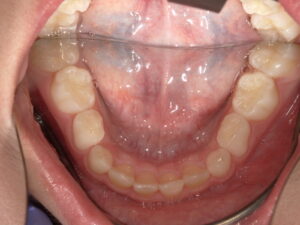

Before

今回は骨格的には問題なく、前歯2本の歯の生える向きがずれてしまっているだけなので リンガルアーチにて上の前歯を前に押し出してあげます。

そうすることで下の前歯2本は何もしなくても自然と内側に引っ込みます。

装置が変形したり、壊れたりして治療期間が長引いてびいてしまいましたが だいたい3~4か月くらいで治ります。

成長してからではこんなに簡単には治りません。